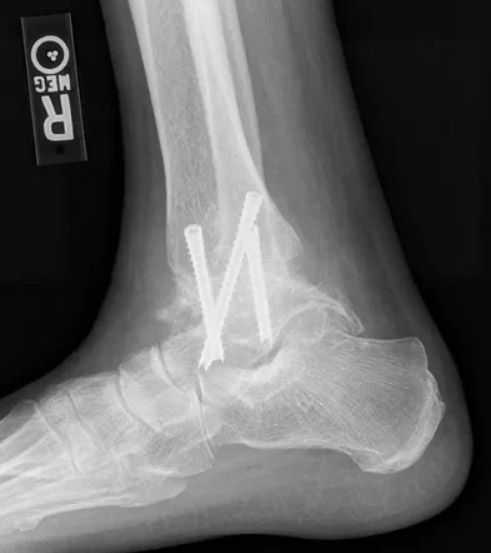

An example of an ankle replacement (total ankle arthroplasty) performed by Dr. Anthony Yi.

X-ray's of the same ankle before undergoing ankle replacement.